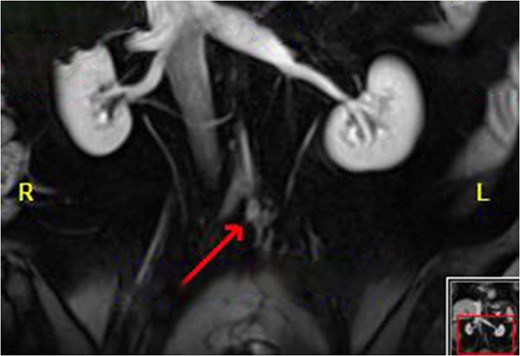

Colonoscopy revealed inflammatory polyps and an ulcerated circumferential mass 30 cm from the anal verge and positive for SCC. Positron emission tomography/computed tomography showed radiotracer uptake in the colon anastomosis, transverse colon, inferior mesenteric artery stump and mesenteric lymph nodes (Figure 1). A 2-cm liver segment VIII lesion was positive for SCC on core needle biopsy (Figure 2).

Liver Metastasis. The red circle indicates the 2-cm site of metastasis.